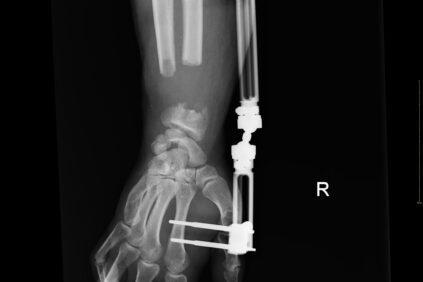

Contamos con la superespecialización de un equipo que se dedica de forma exclusiva a tratar patologías que afectan a mano y muñeca. Dicha superespecialización requiere de conocimientos y experiencia en cirugía ortopédica, plástica, vascular y neurocirugía.

Nuestros servicios en Cirugía de la Mano y Microcirugía.

Abarcamos todas las intervenciones de muñeca, mano y aquellas que requieran microcirugía.

- SuperespecializaciónEn cuestión del órgano vital de la mano

Equipo con amplia experiencia en reconstrucción de extremidades.